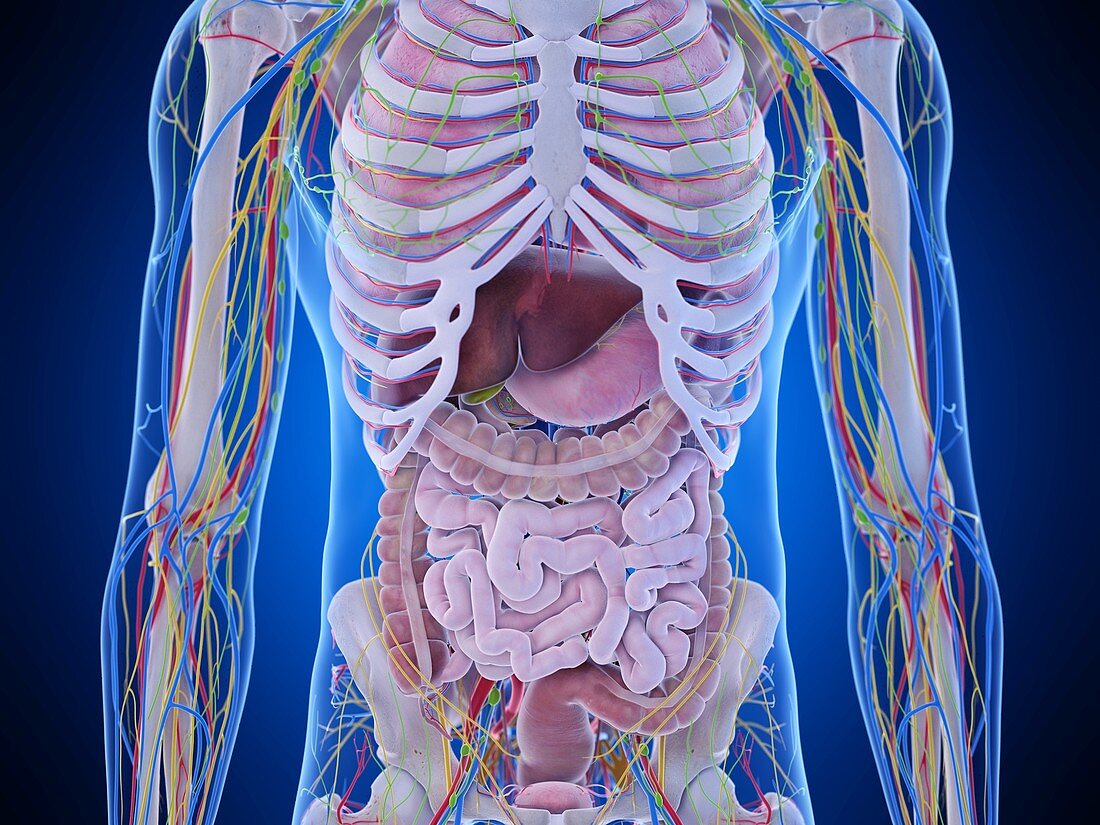

abdomen anatomy model Medically accurate illustration of the abdominal anatomy stock photo

If you are looking for Female abdominal organs, illustration - Stock Image - F026/5554 you’ve visit to the right web. We have 35 Pictures about Female abdominal organs, illustration - Stock Image - F026/5554 like Illustration of human abdominal anatomy in body silhouette. — Digitally, 3d rendered illustration of a females abdominal anatomy Stock Photo - Alamy and also Human Abdomen Model Medical Anatomical Flat Membrane Capsule Structure. Here it is:

Female Abdominal Organs, Illustration - Stock Image - F026/5554

www.sciencephoto.comUpper Abdomin Diagram

www.sciencephoto.comUpper Abdomin Diagram

anatomychart101.storage.googleapis.comIllustration Of Human Abdominal Anatomy In Body Silhouette. — Digitally

anatomychart101.storage.googleapis.comIllustration Of Human Abdominal Anatomy In Body Silhouette. — Digitally

Medically Accurate Illustration Of The Abdominal Anatomy Stock Photo

www.alamy.comabdominal medically accurate

www.alamy.comabdominal medically accurate